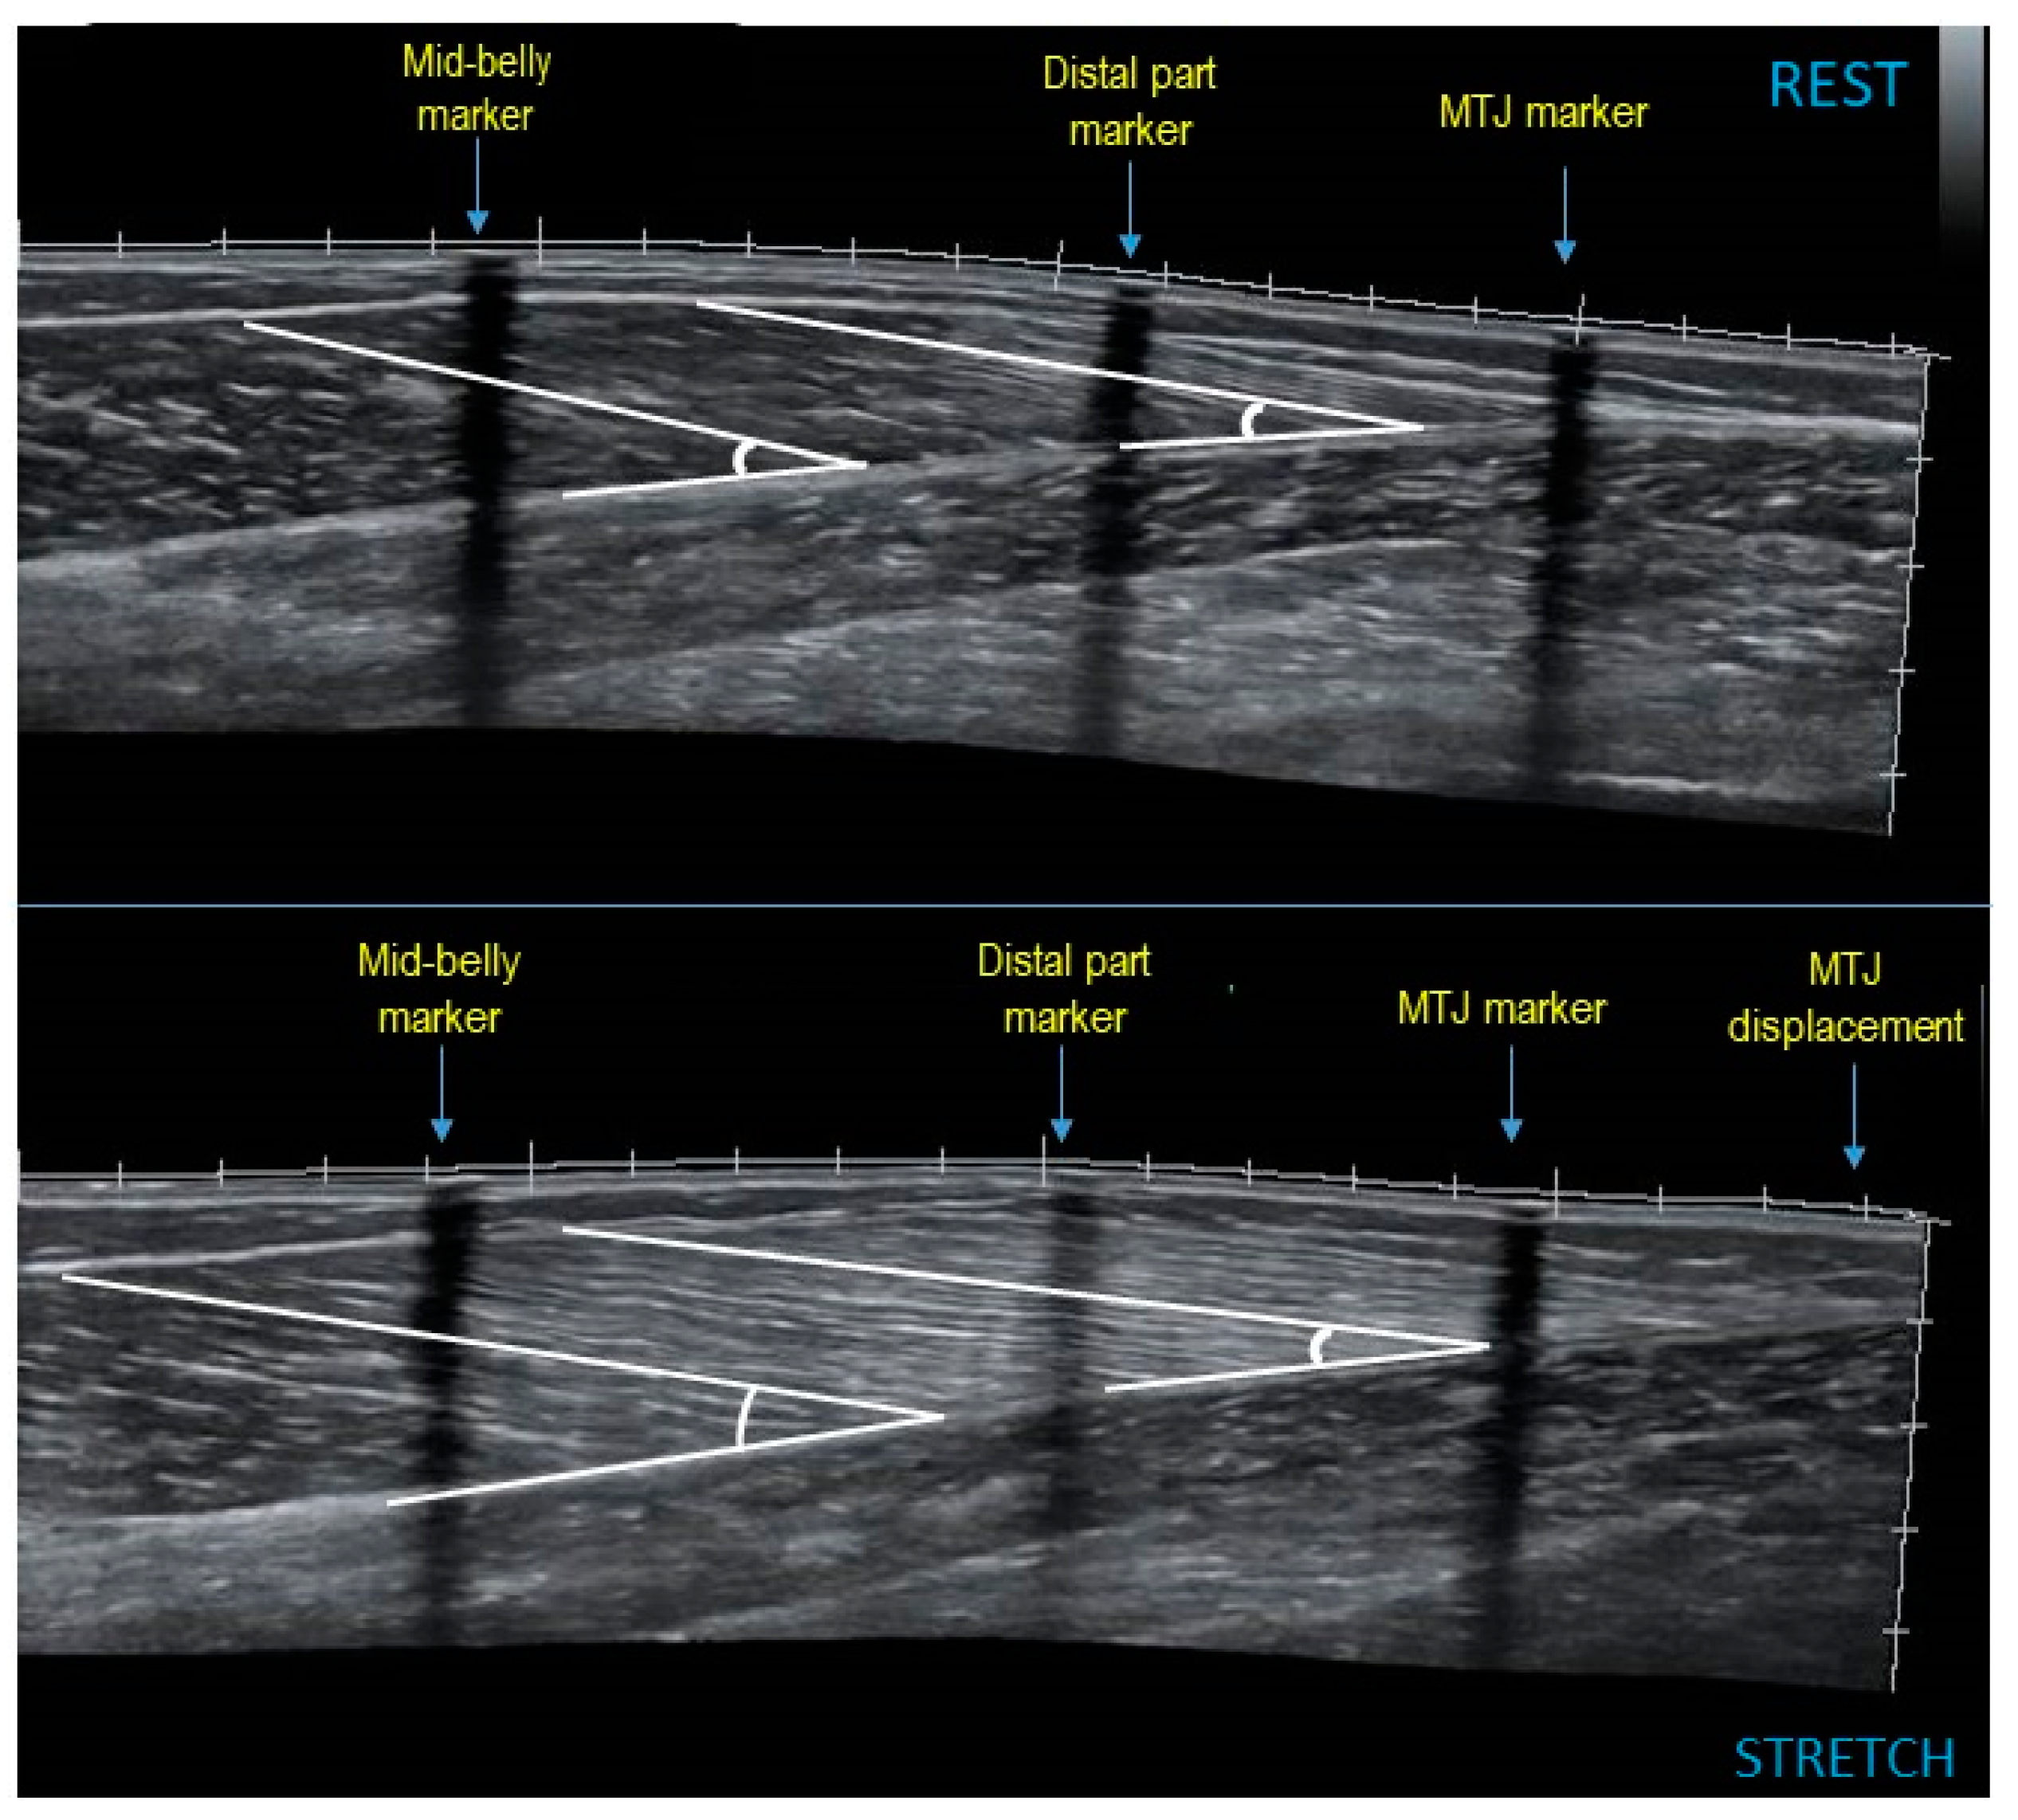

2.4. Resting Muscle Architecture and Ankle Joint Angle

2.5. Muscle Architecture and Ankle Dorsiflexion Angle during Stretching